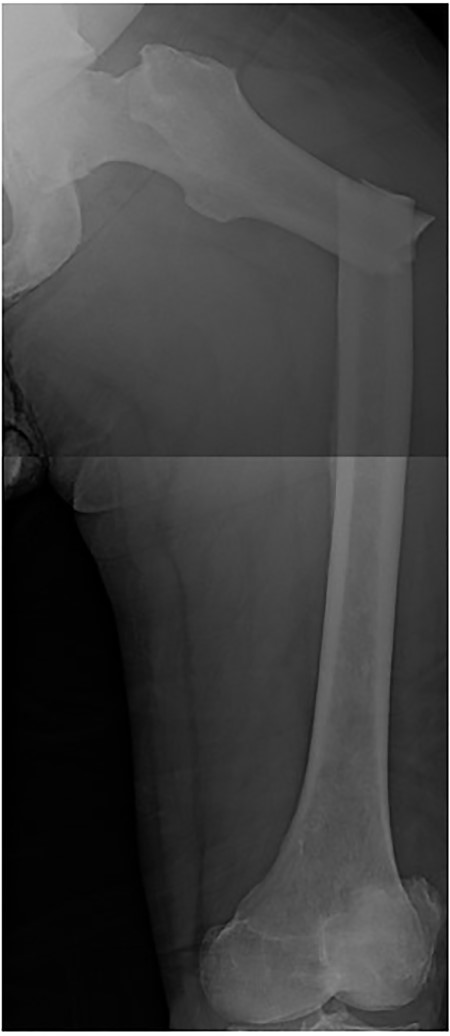

A 60-year-old male, who was diagnosed with Stage 4 prostate adenocarcinoma with known rib metastases and treated with chemotherapy and prostatectomy, sustained a pathologic left transverse subtrochanteric femur fracture after a ground-level fall while ascending stairs at his home. He denied any antecedent left hip or thigh pain. Radiographs revealed blastic metastatic lesions to his left femur (Fig. 1).